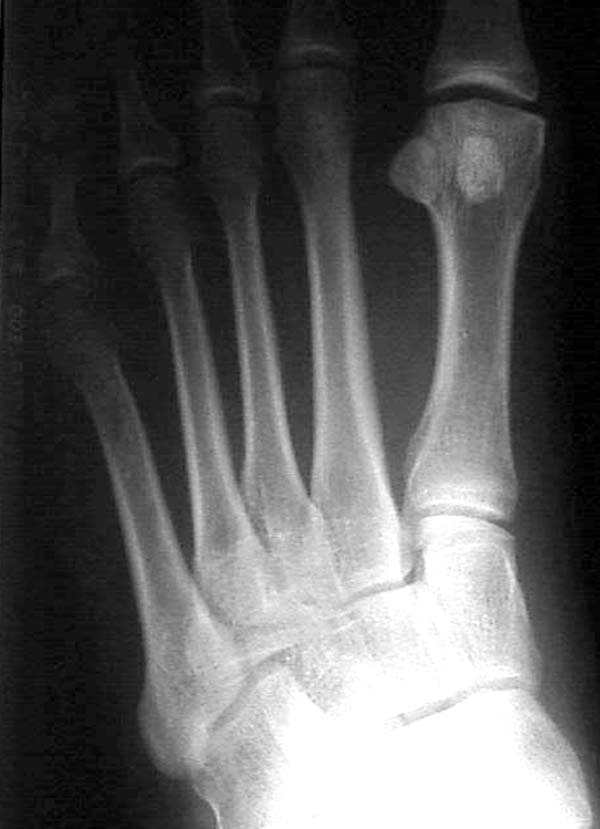

Здесь КТ и сравнительные снимки стопы под нагрузкой.

Диагностировано повреждение медиальной и латеральной колонны.

Если оперативное лечение - как и каким доступом?